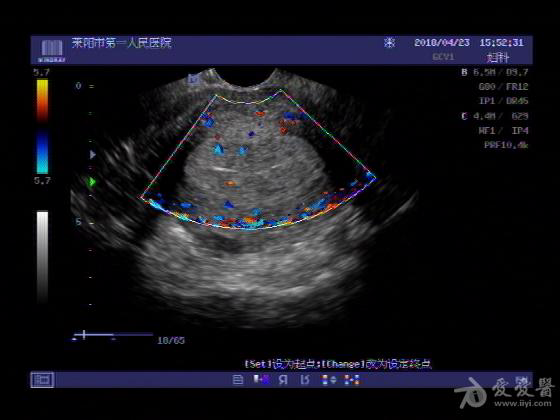

女,48岁,月经量多,两个月,一年前出现过类似现象,刮宫吃药后缓解。

超声可见:子宫内膜显著增厚,后肌壁内膜可见范围约3.27X0.90CM低回声区,CDFI显示较丰富线样血流,宫底宫腔内见类**状低回声结节。前肌壁见多发类圆形低回声结节。

超声提示:子宫内膜增厚(建议刮宫病理),子宫多发肌瘤

病理结果:内膜增生